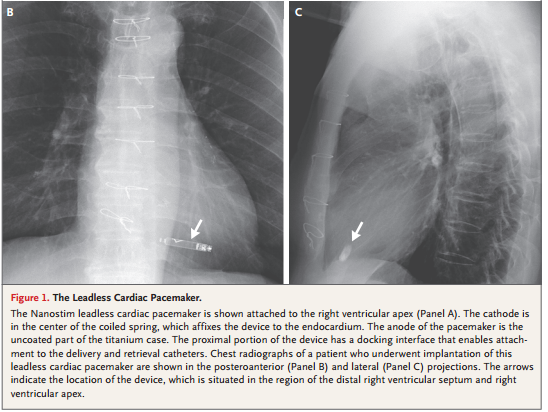

图 无线起搏器经皮植入过程